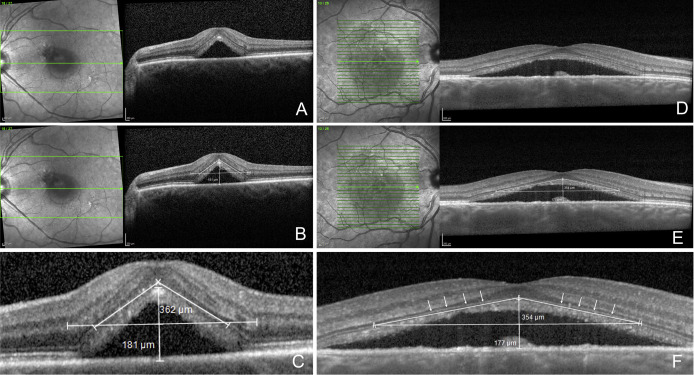

#NEIfunded research from Johns Hopkins Medicine about #AMD biomarkers: Levels of angiopoietin-like 4 and VEGF protein in eye fluid may predict likelihood of developing wet age-related macular degeneration. JCI insight: bit.ly/3OTOfYP